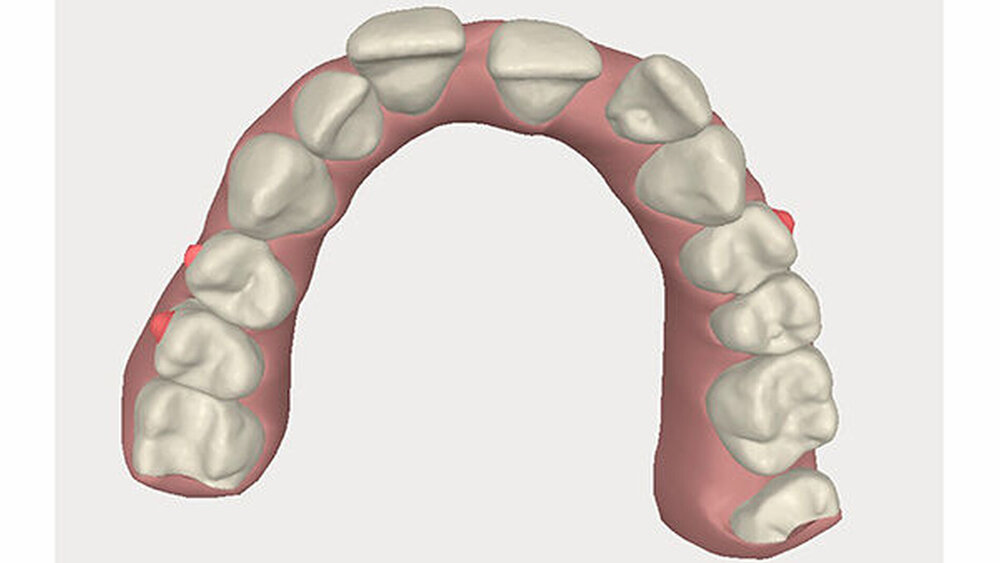

Die Sulkustiefen konnten auf etwas weniger als 4 mm reduziert werden, während der Blutungs- und Plaque-Index bei weniger als 15 Prozent lag. Daher wurde eine kieferorthopädische Behandlung über die nächsten zwei Jahre in Kombination mit engen zahnärztlichen Kontrollen geplant. Als Mittel der Wahl entschieden wir uns gemeinsam mit dem Patienten für das Invisalign-System, da hiermit sowohl eine Schienung als auch eine kraft-arme Bewegung der Zähne möglich sein sollte. Für den Frontzahnbereich wurden keine Attachments geplant, so dass hier eine unnötige Hebelwirkung umgangen werden konnte (Abbildung 3).

Um einen kompletten Lückenschluss im Oberkiefer zu ermöglichen, musste im Unterkieferfrontzahnbereich zusätzlich zur Derotation und Positionierung der Zähne - insbesondere Zahn 41 - von approximaler Schmelzreduktion, kurz ASR , Gebrauch gemacht werden, um einer Tonn`schen Diskrepanz entgegenzuwirken (Abbildung 4).